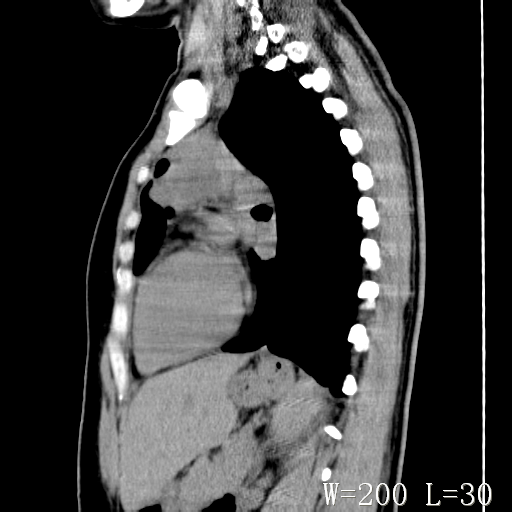

标题: CT27017:1、肺结核?2、永存左上腔静脉。 [打印本页]

标题: CT27017:1、肺结核?2、永存左上腔静脉。

女,32岁,自述肺结核治疗多年复查。

1)考虑左肺上叶肺脓肿,节段性肺不张。2)永存左上腔静脉。

1)考虑左肺上叶节段性肺不张。原因?2)永存左上腔静脉。

支持肺脓肿;还是双上腔静脉确切些吧,回流至冠状窦或右心房。

考虑左肺上叶胸腺瘤可能性大。肺不张/永存左上腔静脉

胸骨后偏左侧囊实性病灶,考虑胸腺瘤可能性大.

1、胸骨后偏左侧囊实性病灶,考虑胸腺瘤可能性大。2、永存左上腔静脉。